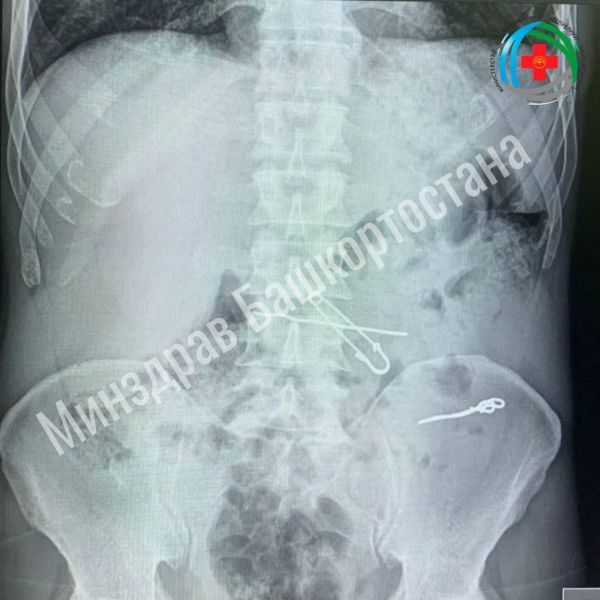

Пациент поступил в медучреждение с болями в животе. Исследования показали наличие в его организме инородных предметов длиной 47,62 и 90 мм. Хирурги провели операцию, удалив из кишечника проволоку и скрепку, а из желудка – булавку и проволоку. Пациент пошел на поправку и вскоре отправился для восстановления домой.